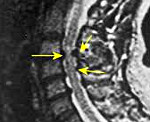

Миелопатия. Обобщенное понятие, используемое в неврологии для обозначения различных по своей этиологии поражений спинного мозга, обычно имеющих хроническое течение. Клинически они могут проявляться нарушениями силы и тонуса мышц, различными сенсорными расстройствами, дисфункцией тазовых органов. Задачей диагностического поиска при миелопатии является выявление причинного заболевания. С этой целью проводится рентгенография позвоночника, МРТ, ЭМГ, ЭНГ, ангиография, анализ ликвора, биохимические исследования крови, ПЦР-диагностика и тд Лечебная тактика основана на терапии основного заболевания, симптоматическом лечении и реабилитации при помощи ЛФК, механотерапии, массажа, иглоукалывания и физиотерапии.

Диагностический алгоритм при выявлении признаков миелопатии направлен на исключение другой, сходной по клиническим симптомам, патологии ЦНС и установление этиологического фактора, лежащего в основе дистрофических изменений спинного мозга. Он включает общий и биохимический анализ крови, рентгенографию позвоночника, МРТ позвоночника, электромиографию (ЭМГ), электронейрографию (ЭНГ), исследование вызванных потенциалов, МР- или КТ-ангиографию спинного мозга, люмбальную пункцию.

По показаниям при отсутствии возможности проведения МРТ в отдельных случаях могут быть выполнены миелография и дискография. При подозрении на инфекционную природу миелопатии проводится исследование крови на стерильность, RРR-тест, ПЦР-исследования, посев спинномозговой жидкости.